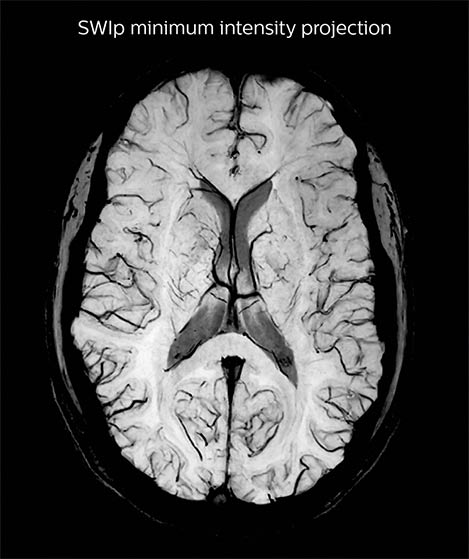

A SWIp image (left) is used to visualize veins in cortical and sub-cortical areas. Using in-house reconstruction techniques, a vascular density map is obtained in individual subjects and averaged over a population (right). Areas in red/green represent areas with dense venous vascularization. The lab uses such images to correct fMRI (BOLD) activation maps in order to minimize false positives.

Sherbrooke SWIp